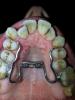

Georgij Опубликовано 22 ноября, 2012 Автор Поделиться Опубликовано 22 ноября, 2012 До операции было так Ссылка на комментарий

Georgij Опубликовано 26 ноября, 2012 Автор Поделиться Опубликовано 26 ноября, 2012 Хотел бы еще узнать, правильный наклон верхних моляров относительно вертикали должен быть в сторону нёба (наклон внутрь) или в сторону щеки (наружу)?По фото слепка можно увидеть, что моляры у меня наклонены "наружу", а премоляры "внутрь".Если правильным является након в сторону нёба, то расстояние между нёбными буграми 6-ок будет меньше при исправлении их положения. Ссылка на комментарий

Force Опубликовано 26 ноября, 2012 Поделиться Опубликовано 26 ноября, 2012 Чуть наружу. Премоляры у вас сильно завалены внутрь. При расширении просто брекет системой произойдет расширение именно в этой части. Моляры не расширятся. А при рпе основное расширение было бы именно в зоне моляров, что у вас не нужно. Ссылка на комментарий